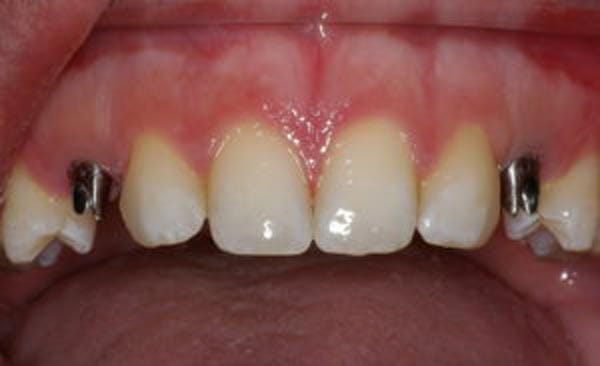

Implants for Failed Root Canals

Many dentists, including Dr. Nazarian, will recommend a dental implant instead of root canal treatment. Dental implants are more affordable in the long run, as root canals often need retreatment down the line and could still ultimately fail.

Some patients are concerned that they will have to leave their implant appointment without a full set of teeth. However, in our office, many patients can and do receive implants and crowns at the same time. Dr. Nazarian has a variety of methods to ensure that no patient leaves without teeth, even if extensive surgery was required.